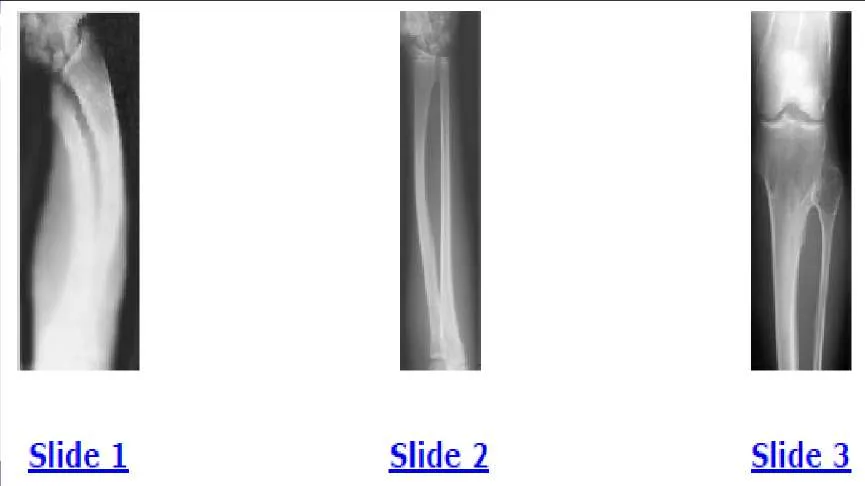

A 12-year-old boy is brought to the clinic by his concerned parents. The boyâ s forearm is bowed, and his parents are confused as to the possible diagnosis and treatment options. You notice that the right forearm of the child is bowed ulnarwards and is shorter compared to the left forearm. The pronosupination is markedly decreased on the right side but is also limited on the left side. The patient has a good grip, pinch, and grasp. He is neurologically intact as well. The parents say that they first noticed the deformity around 6 or 7 years ago, and the mother informs you that she had noticed a hard bump on the forearm. She has recently noticed another bump on his right leg. The child does not complain of pain and is using both of his hands quite well. The parents were informed by a previous physician that the child has Madelungâ s deformity and are concerned that the disease is now involving other areas of his body. You order a radiograph of the patientâ s forearm. The anteroposterior radiograph is shown (Slide). The next step is to order a:

A 12-year-old boy is brought to the clinic by his concerned parents. The boyâ s forearm is bowed, and his parents are confused as to the possible diagnosis and treatment options. You notice that the right forearm of the child is bowed ulnarwards and is shorter compared to the left forearm. The pronosupination is markedly decreased on the right side but is also limited on the left side. The patient has a good grip, pinch, and grasp. He is neurologically intact as well. The parents say that they first noticed the deformity around 6 or 7 years ago, and the mother informs you that she had noticed a hard bump on the forearm. She has recently noticed another bump on his right leg. The child does not complain of pain and is using both of his hands quite well. The parents were informed by a previous physician that the child has Madelungs deformity and are concerned that the disease is now involving other areas of his body. An immediate appointment for magnetic resonance imagine (MRI) and computed tomography (C T) scan are not available, and a genetic evaluation has been carried out previously. As you await the report from the geneticist office, you decide to get a skeletal radiograph series on the patient. The radiograph of the opposite forearm (Slide 1) and right leg are shown (Slide 2). You order a radiograph of the forearm. The anteroposterior radiograph is shown (Slide 3). Your suspected diagnosis is:

A 12-year-old boy is brought to the clinic by his concerned parents. The boys forearm is bowed, and his parents are confused as to the possible diagnosis and treatment options. You notice that the right forearm of the child is bowed ulnarwards and is shorter compared to the left forearm. The pronosupination is markedly decreased on the right side but is also limited on the left side. The patient has a good grip, pinch, and grasp. He is neurologically intact as well. The parents say that they first noticed the deformity around 6 or 7 years ago, and the mother informs you that she had noticed a hard bump on the forearm. She has recently noticed another bump on his right leg. The child does not complain of pain and is using both of his hands quite well. The parents were informed by a previous physician that the child has Madelungs deformity and are concerned that the disease is now involving other areas of his body. You order a radiograph of the forearm. The anteroposterior radiograph is shown (Slide 1). The childâ s skeletal radiograph survey is also presented (Slide 2 and Slide 3). The genetic pattern seen in patients with this type of presentation is:

A 12-year-old boy is brought to the clinic by his concerned parents. The boy s forearm is bowed, and his parents are confused as to the possible diagnosis and treatment options. You notice that the right forearm of the child is bowed ulnarwards and is shorter compared to the left forearm. The pronosupination is markedly decreased on the right side but is also limited on the left side. The patient has a good grip, pinch, and grasp. He is neurologically intact as well. The parents say that they first noticed the deformity around 6 or 7 years ago, and the mother informs you that she had noticed a hard bump on the forearm. She has recently noticed another bump on his right leg. The child does not complain of pain and is using both of his hands quite well. The parents were informed by a previous physician that the child has Madelungs deformity and are concerned that the disease is now involving other areas of his body. You order a radiograph of the forearm. The anteroposterior radiograph is shown (Slide 1). The childâ s skeletal radiograph survey is also presented (Slide 2 and Slide 3). Which of the following areas is unlikely to be involved:

A 12-year-old boy is brought to the clinic by his concerned parents. The boyâ s forearm is bowed, and his parents are confused as to the possible diagnosis and treatment options. You notice that the right forearm of the child is bowed ulnarwards and is shorter compared to the left forearm. The pronosupination is markedly decreased on the right side but is also limited on the left side. The patient has a good grip, pinch, and grasp. He is neurologically intact as well. The parents say that they first noticed the deformity around 6 or 7 years ago, and the mother informs you that she had noticed a hard bump on the forearm. She has recently noticed another bump on his right leg. The child does not complain of pain and is using both of his hands quite well. The parents were informed by a previous physician that the child has Madelungâ s deformity and are concerned that the disease is now involving other areas of his body. You order a radiograph of the forearm. The anteroposterior radiograph is shown (Slide 1). The childâ s skeletal radiograph survey is also presented (Slide 2 and Slide 3). The chance of hand involvement in this child is:

A 12-year-old boy is brought to the clinic by his concerned parents. The boyâ s forearm is bowed, and his parents are confused as to the possible diagnosis and treatment options. You notice that the right forearm of the child is bowed ulnarwards and is shorter compared to the left forearm. The pronosupination is markedly decreased on the right side but is also limited on the left side. The patient has a good grip, pinch, and grasp. He is neurologically intact as well. The parents say that they first noticed the deformity around 6 or 7 years ago, and the mother informs you that she had noticed a hard bump on the forearm. She has recently noticed another bump on his right leg. The child does not complain of pain and is using both of his hands quite well. The parents were informed by a previous physician that the child has Madelungs deformity and are concerned that the disease is now involving other areas of his body. You order a radiograph of the forearm. The anteroposterior radiograph is shown (Slide 1). The childâ s skeletal radiograph survey is also presented (Slide 2 and Slide 3). The most likely complication in this child is:

A 12-year-old boy is brought to the clinic by his concerned parents. The boys forearm is bowed, and his parents are confused as to the possible diagnosis and treatment options. You notice that the right forearm of the child is bowed ulnarwards and is shorter compared to the left forearm. The pronosupination is markedly decreased on the right side but is also limited on the left side. The patient has a good grip, pinch, and grasp. He is neurologically intact as well. The parents say that they first noticed the deformity around 6 or 7 years ago, and the mother informs you that she had noticed a hard bump on the forearm. She has recently noticed another bump on his right leg. The child does not complain of pain and is using both of his hands quite well. The parents were informed by a previous physician that the child has Madelungs deformity and are concerned that the disease is now involving other areas of his body. You order a radiograph of the forearm. The anteroposterior radiograph is shown (Slide 1). The childâ s skeletal radiograph survey is also presented (Slide 2 and Slide 3). The difference between Madelungâ s deformity and this boyâ s condition is:

A 12-year-old boy is brought to the clinic by his concerned parents. The boys forearm is bowed, and his parents are confused as to the possible diagnosis and treatment options. You notice that the right forearm of the child is bowed ulnarwards and is shorter compared to the left forearm. The pronosupination is markedly decreased on the right side but is also limited on the left side. The patient has a good grip, pinch, and grasp. He is neurologically intact as well. The parents say that they first noticed the deformity around 6 or 7 years ago, and the mother informs you that she had noticed a hard bump on the forearm. She has recently noticed another bump on his right leg. The child does not complain of pain and is using both of his hands quite well. The parents were informed by a previous physician that the child has Madelungs deformity and are concerned that the disease is now involving other areas of his body. You order a radiograph of the forearm. The anteroposterior radiograph is shown (Slide 1). The childâ s skeletal radiograph survey is also presented (Slide 2 and Slide 3). All of the following are acceptable options, either alone or in combination, for management of this childâ s condition, except:

Question 46: